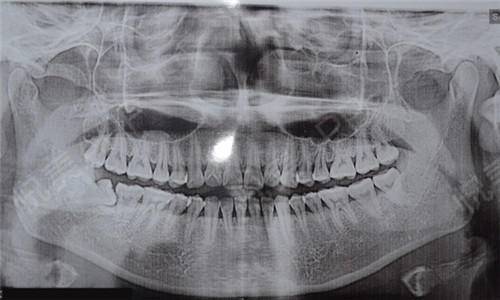

先要做一个口腔全景片、颌骨CT等。查看口腔的具体情况,是否有炎症、牙槽骨吸收等情况。然后,医生会询问患者全身的病史,可能需要查血常规、出凝血时间、血压、血糖、乙肝5项、脉搏等。确定能手术后,才会诊断去模、指定种植牙方案。(第一次大约1个多小时)